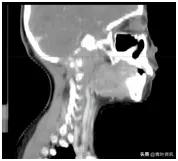

这可把珊珊爸爸妈妈急坏了,辗转多家大医院,颈部核磁共振检查发现颈椎、枕骨骨质广泛破坏、周边软组织形成(图一),后经病理检查确诊为朗格汉斯细胞增多症,是一种良性病!

图一 治疗前CT

但是随后医生的交待又让他们凉了半截,因骨质破坏范围较大,且位置特殊,无法手术治疗,如果病情进一步发展,随时可能出现颈椎骨折危及生命。